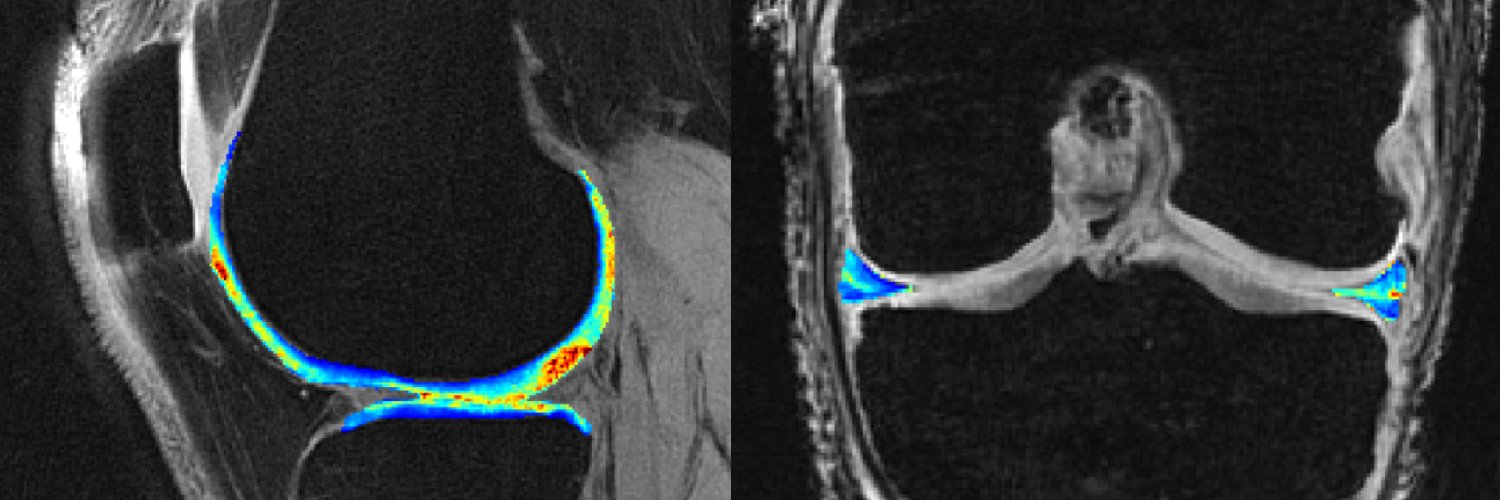

Associate Scientist @ Hospital for Special Surgery. Biomedical engineer doing MSK MRI for meniscus, cartilage, ligament, and total joint replacement.